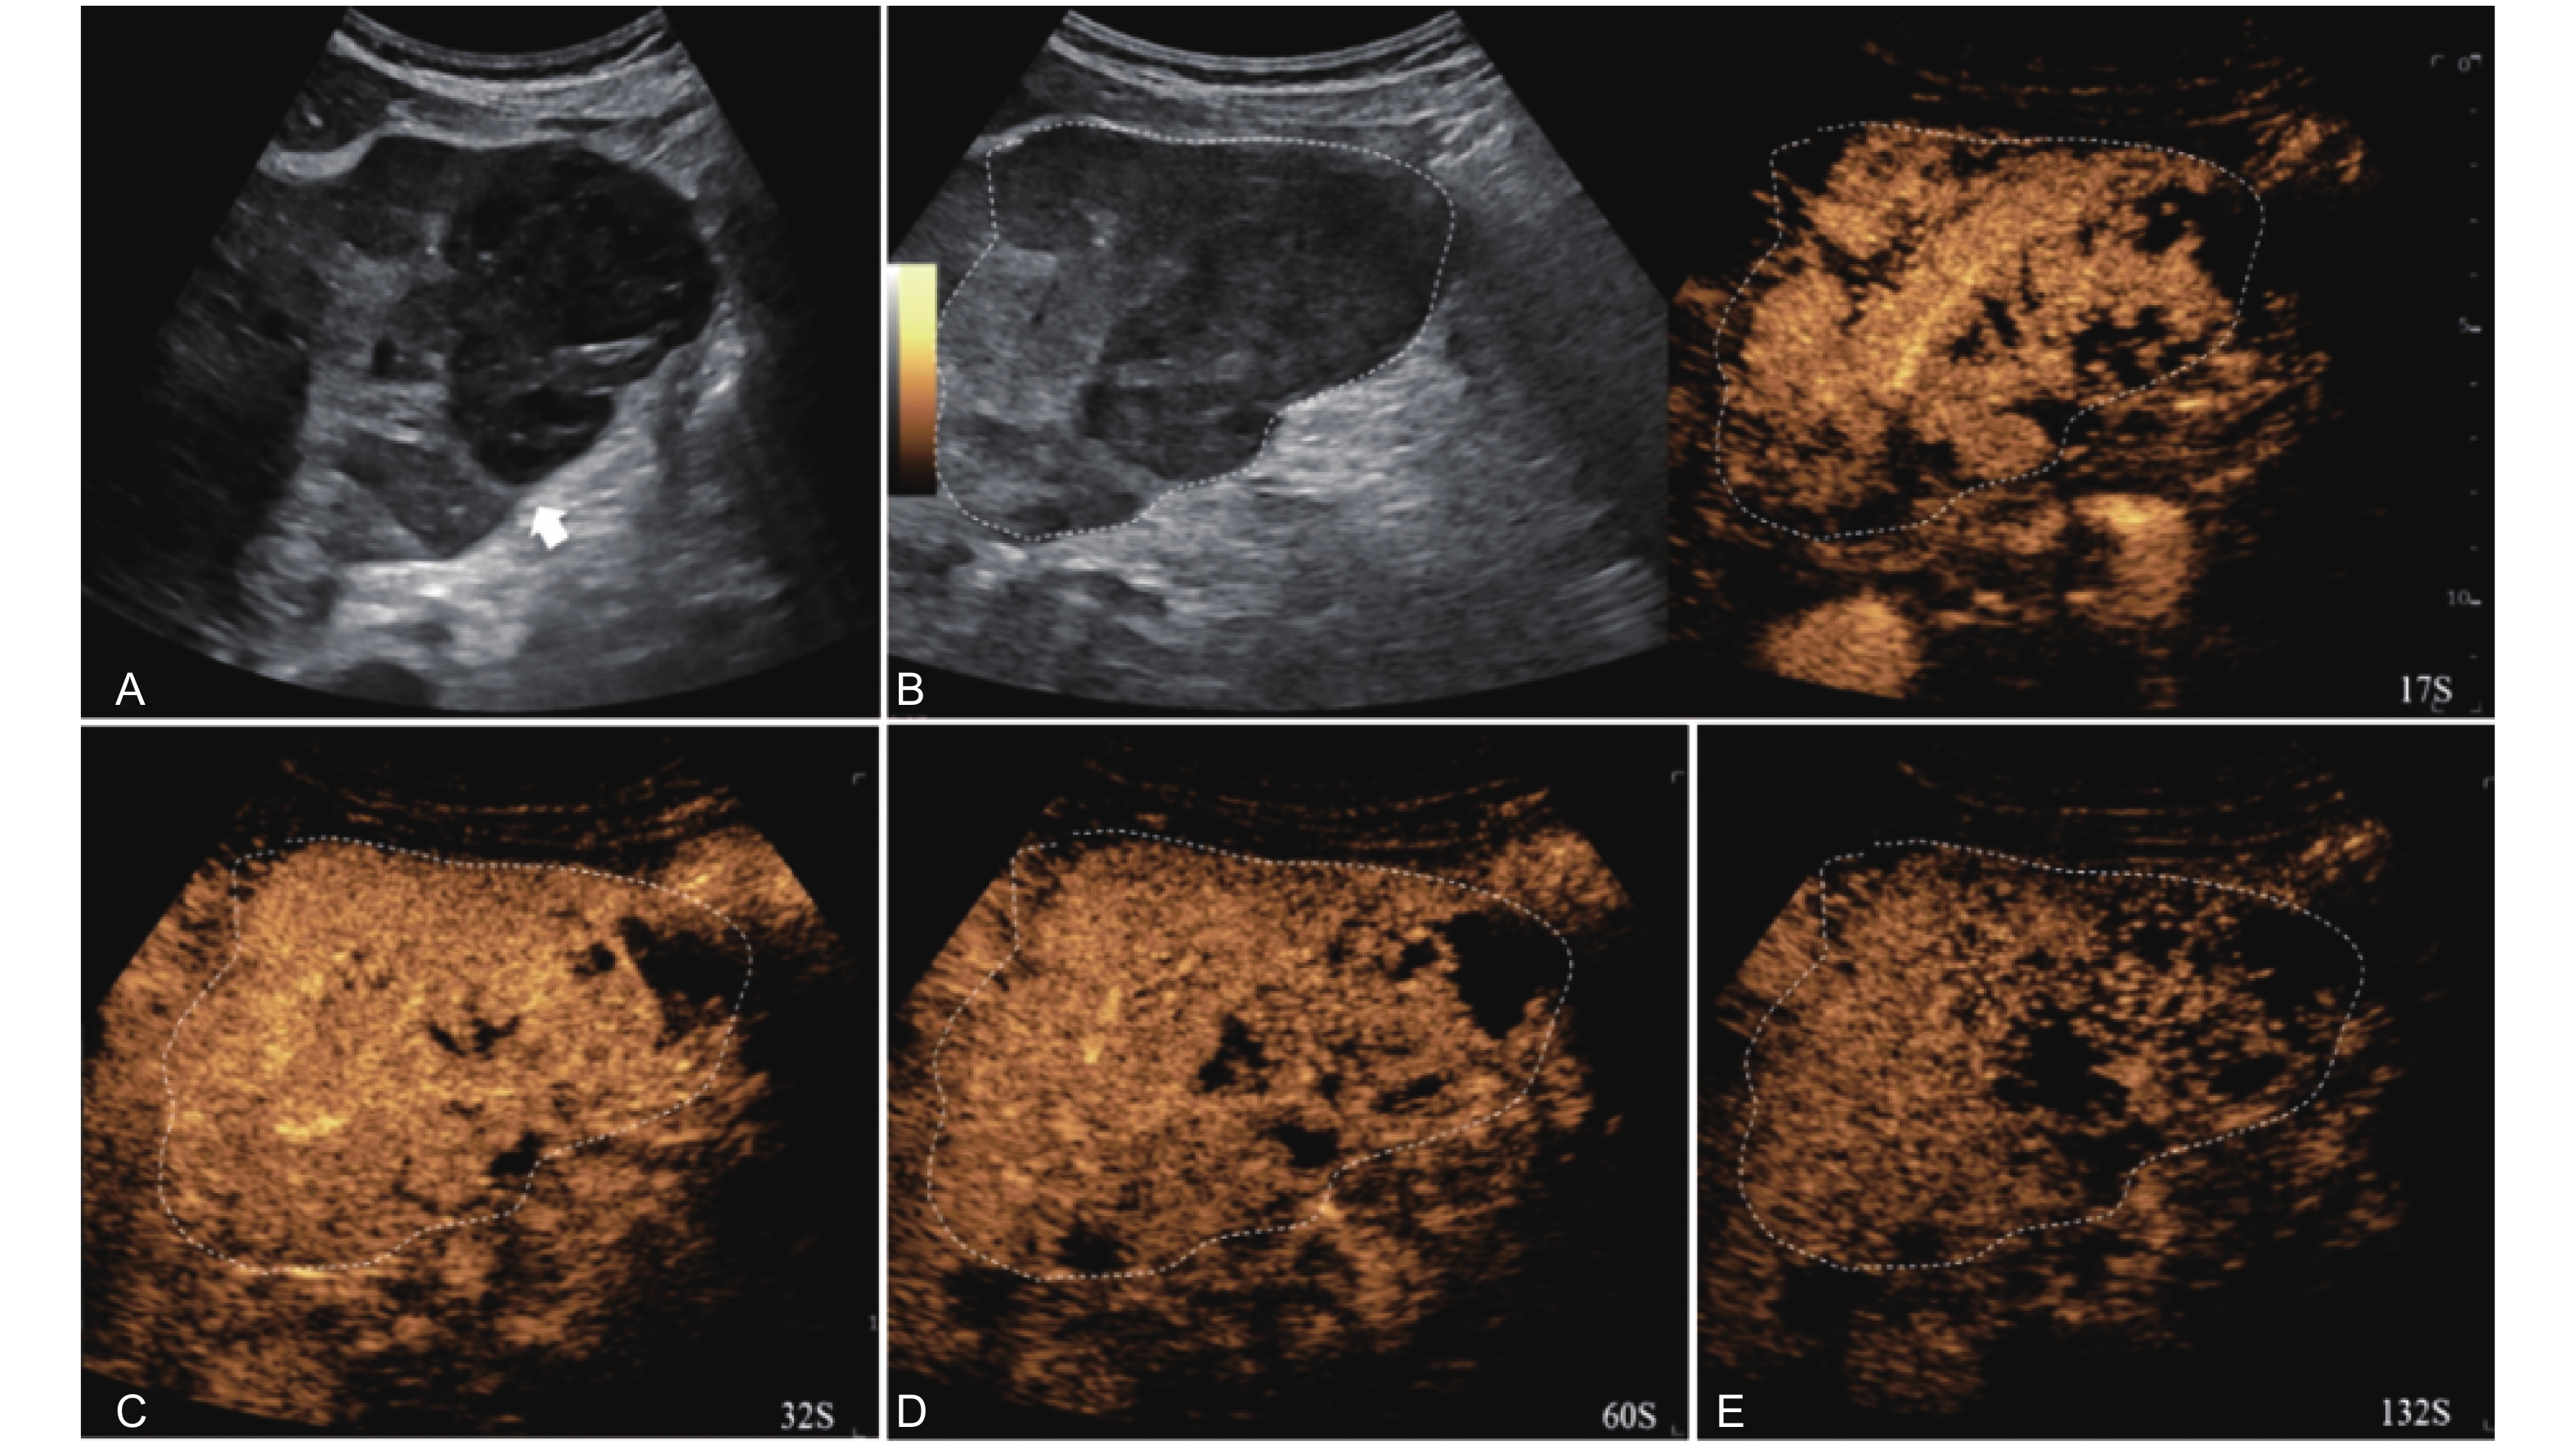

Figure 10

LR-TR Viable. A 56-year-old male with HCC, 1 year after RF ablation. (A) B-mode image shows a heterogeneous mildly hypoechoic lesion (thick arrow) with poor-defined margins in segment VII; (B) Post-treatment CEUS shows intralesional heterogeneous hyperenhancement; (C) The lesion shows mild washout in the portal venous phase; (D) The lesion shows marked washout in the late phase. Perilesional enhancement remains identical to the surrounding liver parenchyma throughout all phases. Findings are consistent with LR-TR Viable. (This case and figures were contributed by Dr. Qiang Lu from Huaxi Hospital of Sichuan University)"